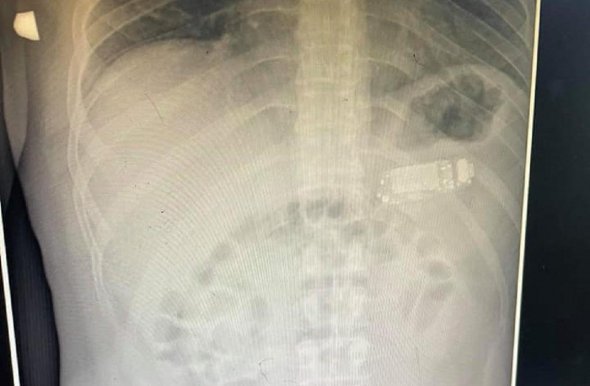

У Косово чоловік проковтнув мобільний телефон Nokia 3310, 2000 року випуску.

Телефон застряг у животі 33-річного потерпілого, пише Metro.

Шлунок не зміг переварити мобільник через його розміри. Лікарям довелося оперувати чоловіка. Медики вийняли пристрій частинами, не розрізаючи шлунок. Операція відбулася без ускладнень.

Водночас отруйні речовини з акумулятора могли витекти та серйозно нашкодити чоловікові.